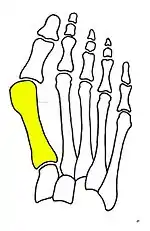

Syndesmosis procedure addresses specifically the two fundamental problems of metatarsus primus varus deformity that gives rise to the bunion deformity. They are leaning and instability of the first metatarsal bone . Syndesmosis procedure uprights the leaning first metatarsal bone with strong binding sutures between it and the second metatarsal bone (Fig. 2) and then also stabilizes it uniquely by creating a fibrous connecting bridge between these two bones (Fig. 3, 4). First metatarsal bone can be readily realigned because by definition of the metatarsus primus varus deformity its first metatarsal is abnormally loose and mobile.